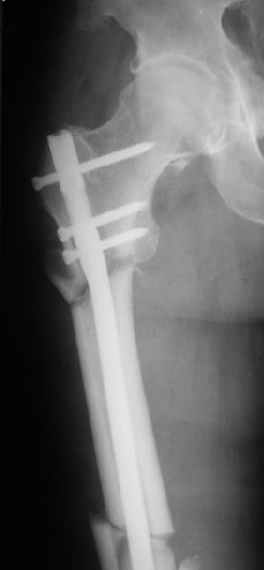

При межвертельных переломах с цефаломедуллярными гвоздями бывает, что проксимальый винт проходит или черед периферический отломок, или прямо над ним. И если остался диастаз, то этот винт при осевой нагрузке не дает сблизиться отломкам. Пример такого остеосинтеза в застарелом случае в приложении.

В качестве предупреждающей меры можно долотом разрушить латеральную стенку дистального отломка под винтом.

Могу скромно напомнить о существовании стержня нашей модификации.

В частности, на проксимальном конце сделано еще одно дополнительное статическое отверстие. Можно ввести в проксимальном отделе 4 винта, из них 3 статические (2 в круглые отверстия и 1 по нижнему краю овального). Картинки в приложении. На дистальном конце стержня тоже кое-что улучшено. Спрашивайте в аптеках, как говорится. Выпускается предприятием "ЦИТО" (Москва), то есть это малобюджетное решение.

Это было года 2,5 назад, мы тогда еще уточняли возможности шинирования с угловой стабильностью гвоздем с поперечным расположением винтов при переломах проксимального отдела бедра. Пациенту не пришлось приобретать намного более дорогой рекон или проксимальный гвоздь. В приложении еще несколько примеров применения того гвоздя при высоких переломах бедра, в том числе с более латеральной точкой входа. Гвоздь изгибаем для этого.